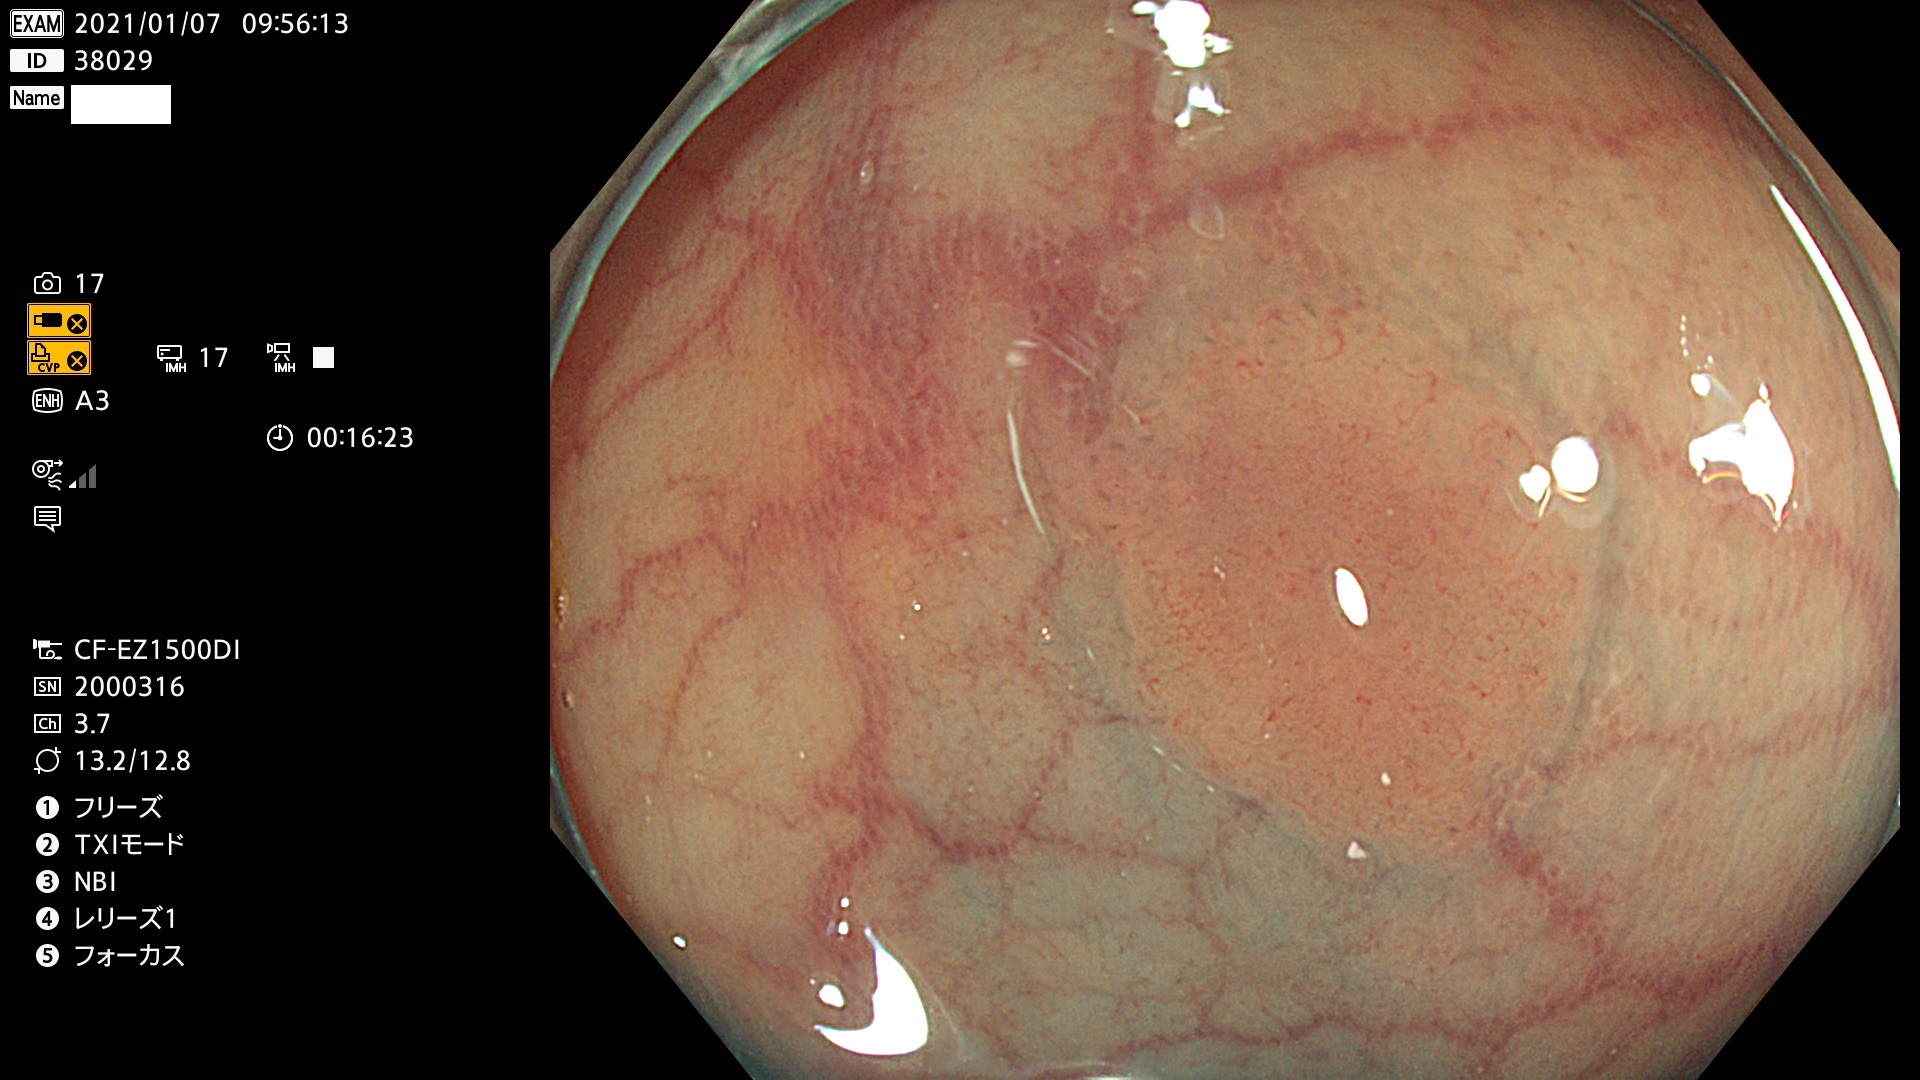

38001 38002 38003 38004 38006(SSAPのみ) 38007 38008 38009 38010 38012 38013 38014 38016 38018 38020 38021 38025 38026 38029 38032 38033 38034 38035 38036 38037(SSAPのみ) 38039 38043 38044 38048 38049 38050 38052 38055 38056 38057 38058 38059 38064(SSAPのみ) 38065 38068 38069 38070 38071 38072 38074 38075 38076 38078 38079 38080 38082 38083 38084 38085(SSAPのみ) 38086 38087 38088 38089 38090 38091 38092 38093 38094 38097 38098 38099

発見困難で危険性の高い平坦型病変(上記100名より抽出)